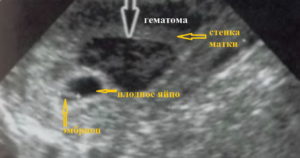

Вместе с отслоением хориона начинают разрываться сосуды, за счет которых он внедрился в матку, в этой области образуется гематома. Именно это и будет самым первым симптомом отслоения, которое обнаруживается на ультразвуковой диагностике. В случае частичной или не сильно выраженной отслойки, гематома может быть единственным проявлением данного патологического состояния.

Очень важно отметить, что любая женщина, даже абсолютно здоровая, может столкнуться с угрозой прерывания беременности. Плодное яйцо начинает отделяться от оболочки, хориона и это является началом выкидыша. В месте отслойки появляется ретрохориальная гематома. Постепенно она начинает расти и происходит полное отслоение плодного яйца, что называется самопроизвольным абортом.

УЗИ-исследование – это основной способ диагностики этой патологии наряду с общим осмотром врача гинеколога. С помощью ультразвука доктор сможет увидеть наружную оболочку плодного яйца и оценить, в каком она состоянии. Также для него будет важным наличие гематомы между плодным яйцом и хорионом, то есть его оболочкой.

Это происходит тогда, когда отслаивается не вся оболочка, а только какая-то ее часть. На УЗИ определяется наличие гематомы, а женщина заявляет о наличии кровянистых выделений.

Плодное яйцо начинает отторгаться от хориона, здесь образуется ранка вследствие повреждения сосудов, за плодной оболочкой скапливается кровь, образуя гематому, из-за чего это явление в акушерстве называется еще ретрохориальной гематомой.

Отслойка плодного яйца – это начало самопроизвольного аборта (выкидыша). Яйцо начинает отделяться от плаценты, повреждая тем самым сосуды. В месте разрыва образуется гематома. Она начинает увеличиваться, вызывая дальнейшее отслоение.